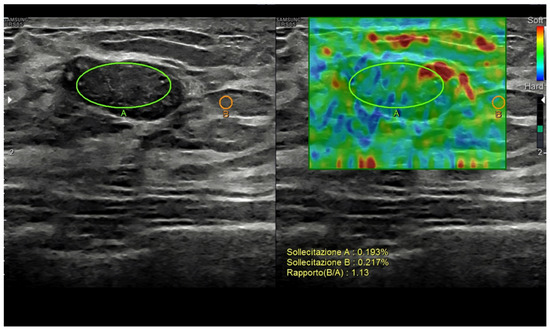

2.4. Elastography

US elastography measures small tissue motions due to pressure forces, i.e., the viscoelastic properties of breast abnormalities [40]. Current techniques include strain elastography, based on the manual pressure from the operator; acoustic radiation force impulse imaging (ARFI); point shear-wave elastography; and 2D/3D shear-wave elastography, based on the changes provoked from the focused ultrasounds themselves. Based on the different techniques, qualitative (subjective scoring), semi-quantitative (strain-to-fat ratio), and/or quantitative data can be obtained [7,8,37,41,42,43,44,45,46,47,48,49].

The use of elastography has been mostly focused on breast nodule characterization, but aspects such as tumor detection, tumor extent assessment, axillary lymph node status, percutaneous procedure guidance, and tumor response to treatment assessment must also be considered [41,50,51,52]. As a general rule, stiffer nodules (i.e., score 1 or 2, low strain ratio, low shear-wave speed), opposing a significant resistance to the changes, are thought to be malignant, while elastic ones (i.e., score 4 or 5, high strain ratio, high shear-wave speed) are usually categorized as benign [53] (Figure 4).

Figure 4. Breast fibroadenoma. Strain ratio allows a semi-quantitative assessment of the lesion-to-fat stiffness.